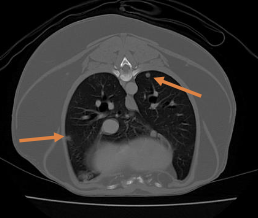

what imaging modalities are used in the diagnostic work-up for STS?

-3 view chest rads

- +/- abdominal imaging (consider with subtype, high grade pelvic limb STS)

- +/- advanced imaging (CT or MRI) for tx planning

what is the most common site of metastasis of STS?

lungs most common

(in general, STS mets are rare, but depends on grade)